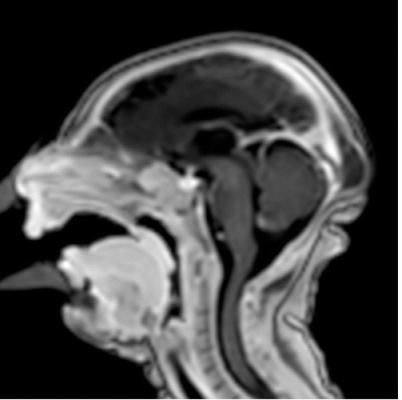

Many of the adults had symptoms of Guillain-Barré syndrome, a rare disorder in which the body's immune system attacks the nervous system, causing rapid onset muscle weakness. A few showed inflammation of the brain and spinal cord (Bickerstaff's encephalitis), or brain stem and spinal cord lesions. Common magnetic resonance imaging (MRI) findings included enhancement of certain spinal and facial nerves. In the newborns, MRI showed orbital injuries and anatomical changes in brain tissue.

In a third study, ultrasound and fetal MRI were performed on pregnant patients with Zika virus infection at different gestational ages. Once the babies were born, they underwent ultrasound, CT and MRI. The researchers then created 3-D virtual and physical models of the skulls. More than half the babies had microcephaly, brain calcifications and loss of brain tissue volume, along with other structural changes.